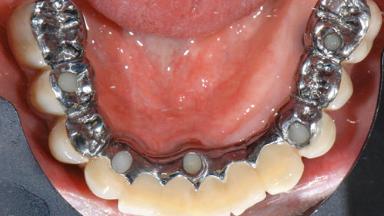

Repeated Acrylic Fractures on a Mandibular Fixed Full-arch Implant-supported Metal/Acrylic Prosthesis

A 77-year-old male patient was referred for the management of frequent and repeated acrylic fracture of his existing mandibular fixed full-arch implant-supported metal/acrylic prosthesis. He also complained about softtissue soreness and the lack of retention and stability of his maxillary removable partial metal/acrylic prosthesis. Both prostheses had been delivered two years previously as part of his full-mouth rehabilitation (caries, tooth wear, tooth fracture). His medical history revealed high blood pressure, controlled with the use of antihypertensive medication.

# of Implants 5

Type of Implants Two-Piece

Prosthesis Type FDP

Retention Screw-retained, with 4 or more splinted implants Screw-retained, with 4 or more splinted implants